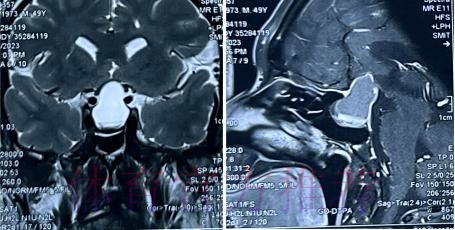

从恐慌到冷静 影像学检查给出的真实答案

在高速对抗的现代足球里 现场肉眼和赛后情绪往往会放大对伤情的判断 一名球员倒地呻吟或无法坚持比赛 很容易被解读为韧带断裂 或肌肉严重撕裂 但真正决定恢复周期的关键因素 通常要到核磁共振检查之后才会明朗 因为核磁能在较早阶段清晰显示软组织 肌肉 韧带以及骨结构的微小损伤情况 对伤情做出更接近真相的分级判断 塞巴略斯此次就是典型案例 初步观感可能让人联想到更严重的伤病 但核磁提示伤情相对可控 没有出现完全断裂或大面积撕裂 也就意味着他不需要漫长的康复旅程 只要遵循医学建议 科学负荷管理 就有机会用较短的时间重新回到训练场和比赛中

塞巴略斯这一类型的技术中场 通常触球频繁 变向急促 需要大范围穿插跑动 在这种比赛习惯下 肌肉和韧带承受的累积负荷极高 尤其在密集赛程和高压对抗中 任何一次小小的失衡或强硬对抗 都可能放大为潜在伤病 因此外界对他伤情格外敏感 并非夸张反应 而是基于过往大量案例得出的经验判断 从厄德高 德布劳内 再到其他同类型中场 很多球员都在职业生涯某个阶段与伤病长期共存 一旦错过最佳治疗和恢复窗口 轻伤有可能拖成旧患 进而影响球员的爆发力 节奏控制能力乃至职业寿命 在这一背景下 经核磁共振检查确认 塞巴略斯伤情没有预期严重 其实反映的是球队在医疗体系 与负荷管理上的相对成熟 至少在第一时间 做到了科学评估 而不是情绪化处理